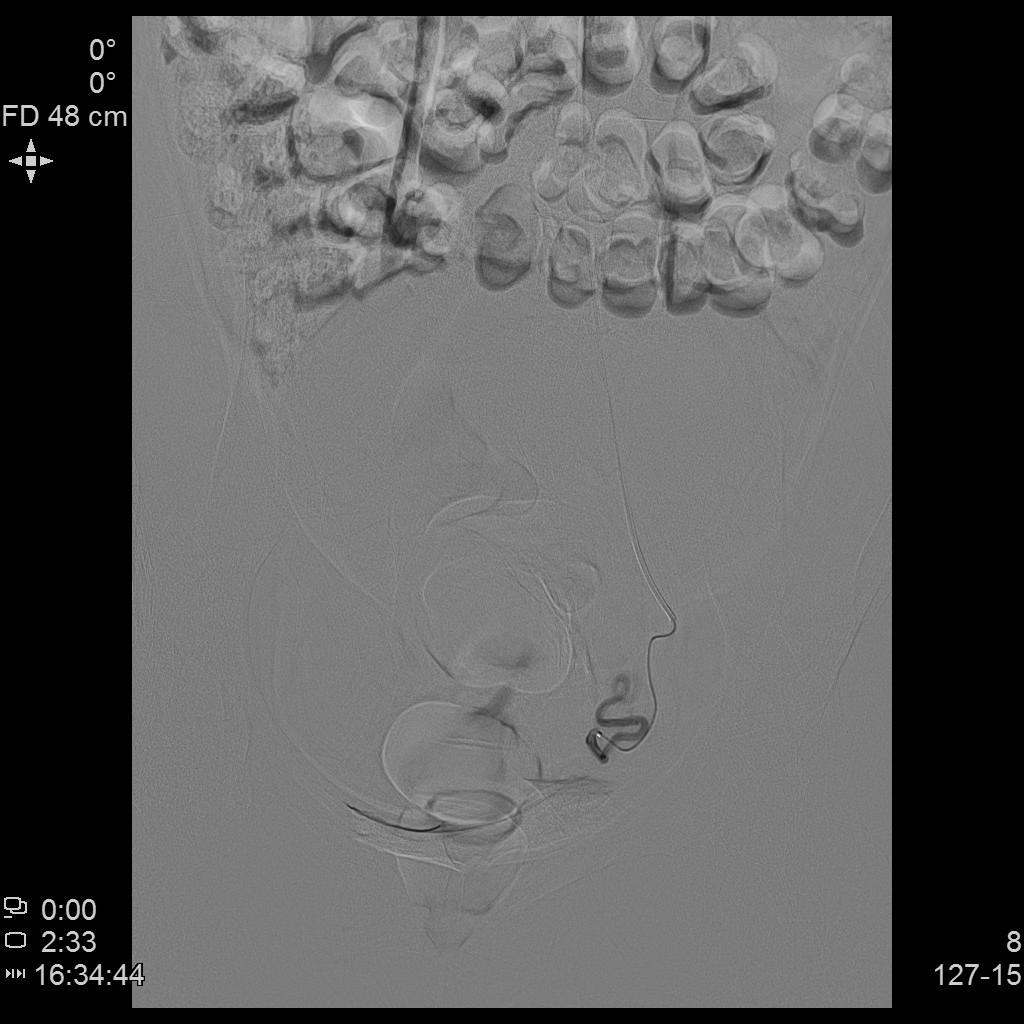

- 进一步超选插管右侧髂内动脉造影确认子动脉开口位置。

右侧髂内动脉造影

- 微导管进一步超选插管右侧子宫动脉主干造影确认位置。

右侧子宫动脉造影

- 进一步超选插管左侧髂内动脉造影确认子动脉开口位置。

左侧髂内动脉造影

- 微导管进一步超选插管左侧子宫动脉主干造影确认位置。

左侧子宫动脉造影

- 术后桡动脉止血器压迫止血8小时,患者术后无需长时间卧床、下肢制动,舒适度大大提升,利于术后快速康复。

桡动脉压迫止血器